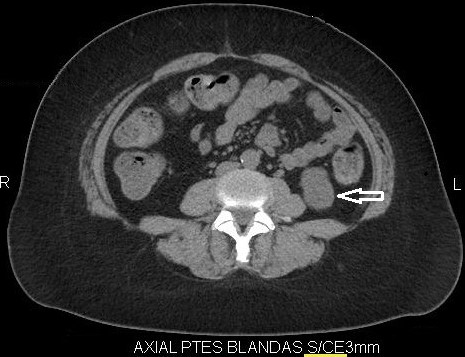

Fase sin contraste o basal

En la exploración renal se debe incluir esta frase dentro del protocolo; la fase proporciona la información inicial de una masa tumoral sospechosa, lo que permite tener un punto de referencia al compararse con las fases post-contraste. Los valores mayores a 12 UH son sospechosos de malignidad; teniendo en cuenta que el CCR es un tumor vascularizado, su atenuación aumenta a 20.

UH o más; si dichos tumores son mayores a 3 cm tienen características más heterogéneas en comparación con los tumores menores a 3 cm, que son más homogéneos.

Las calcificaciones se encuentran hasta en un 30% de los CCR y son más fácilmente visibles durante la fase basal 3-4 (Fig. 1).